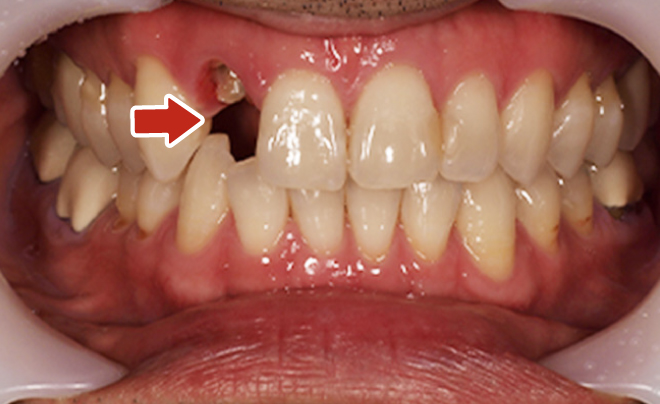

Before

After

| 45歳 男性 | 医療関係者紹介 |

|---|---|

| 主訴 | 右前歯が取れた(右上2) |

| 処置内容 |

1本インプラント埋入+再生療法 抜歯即時埋入⇒抜歯を行い、同時にインプラント埋入(即時埋入) |

| 治療費用 | 上顎: 約40万円(税込) |

| 治療期間 | 約11ヶ月 |

| リスク | 上部構造物、仮歯の破折、術後の腫れ(3日)、人工歯根脱落リスクがあります |